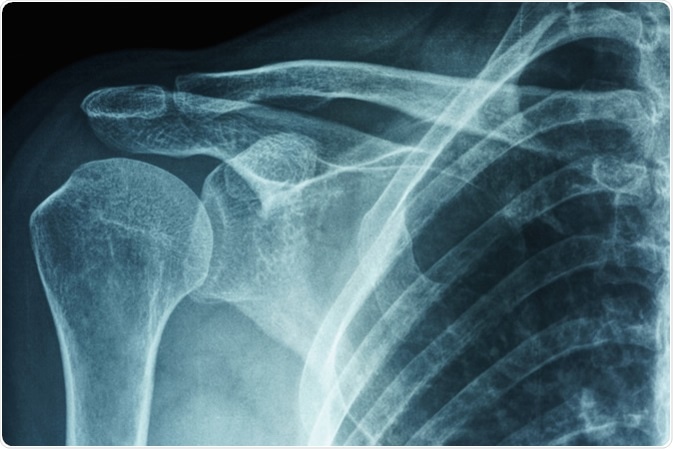

Frozen Shoulder

A frozen shoulder (adhesive capsulitis) is a condition that causes stiffness and pain on the shoulder joint. The signs and symptoms include severe pain, limited range of motion, and stiff shoulder joint. The symptoms begin gradually and worsen over time. It typically resolves within one to three years.

X-ray film of primary frozen shoulder or adhesive capsulitis of Asian female patient. Image Credit: PK289 / Shutterstock